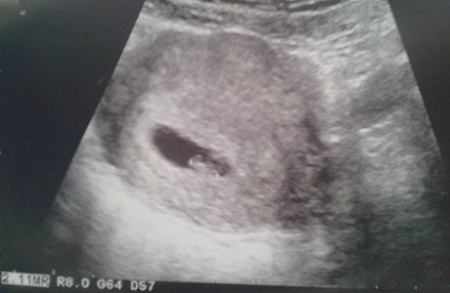

A vizsgálatok még messze vannak, viszont egy privát klinikán történt ultrahangon már túl vagyunk. Ennek a vizsgálatnak is oka volt, mivel pár napja ismét véreztem. Megint jött a pánik, az elkeseredettség, viszont most valami más volt. Kiderült, hogy kettő babánk volt, csak sajnos az egyik iker felszívódott, és a hátramaradt petezsák ürült ki. Viszont a másik picike jól van, és ez az, ami számít jelen pillanatban.

És hogy honnan jött a cikk címe? Kislányom, Molly nevezte el a babát Charlie-nak. Nem tudom, hogy honnan szedte, de rajta maradt. Molly pedig napokig lelkesen lobogtatta az ultrahangon készült képet.